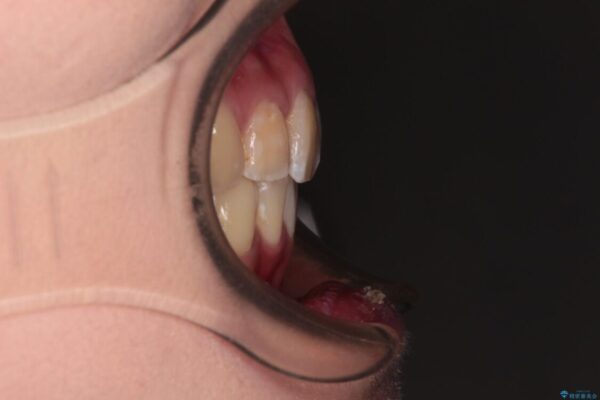

内側に倒れ込んだ歯や下の前歯が隠れてしまうほどの咬み合わせを改善したいとのことで来院された患者様です。

下顎の叢生を解消するために抜歯が必要であり、奥歯の咬み合わせや口元の印象から、上顎も同様に抜歯と判断し、上下左右の第1小臼歯4本抜歯してワイヤー装置にて矯正治療を行うこととしました。

咬み合わせが深く、そのままでは上顎の抜歯スペースが閉じきらない可能性があったため、治療初期から深い咬み合わせを改善させるように試みました。

実際にはなかなか改善されず、当初予定よりも治療期間がやや長期化してしまいました。

治療途中

• デコボコと深い咬み合わせ ワイヤー装置での抜歯矯正 治療途中画像